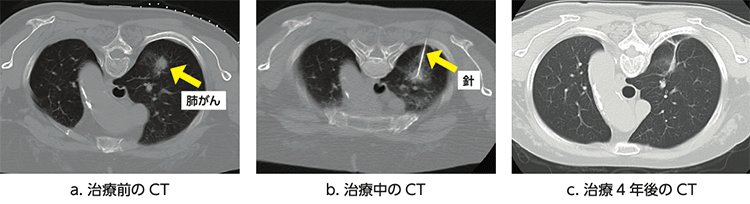

- CTや超音波検査を行い、皮膚から腫瘍までの針を刺す経路を決定します(写真、図a)。

- 針を刺す部分の皮膚を局所麻酔し、CTや超音波の画像検査で位置を確認しながら、直径約1.5mm程度の針を皮膚から直接刺し、目的の腫瘍まで進めます。

- 針の位置が適切であることを確認したら、針の先端にラジオ波電流を流して焼灼を開始します(図b)。治療中は、強い痛みが生じることがあるため、必要に応じて麻酔薬や鎮痛剤(痛み止め)を投与します。

- 術後は定期的に画像検査をして、治療効果の評価を行います(図c)。